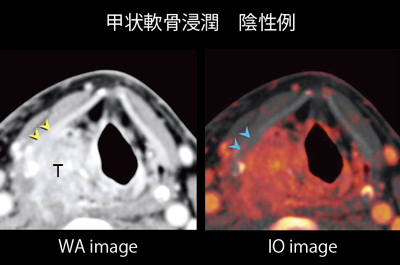

Ct検査よりがん組織と正常組織の区別が明確でct検査とは異なる情報からがんの深さや広がりリンパ節への転移の有無を調べます 7超音波エコー検査 首の表面から超音波をあ てそのはね返りをモニターで見ながら確認. 下咽頭癌の進展範囲を読影する際のチェックポイント 腫瘍の最大径 喉頭への進展の有無 軟骨浸潤の有無 上下方向への進展範囲の決定中咽頭頸部食道 軟部組織浸潤の有無特に梨状癌 梨状窩尖部への進展の有無.

頸部 Dual Energy Ctを用いた喉頭癌と下咽頭癌による喉頭軟骨浸潤評価